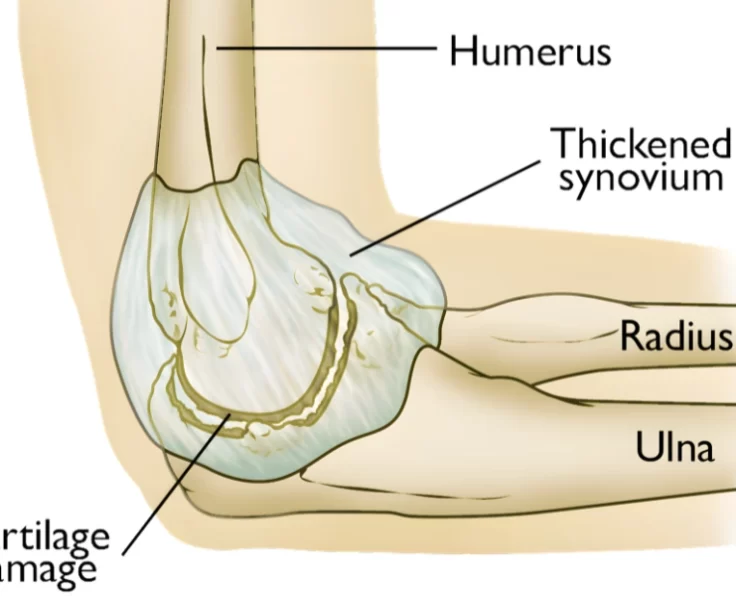

Elbow Arthroscopy

The term arthroscopy comes from Greek words that refer to the joint. In modern surgery, your surgeon uses a small camera and a video monitor…

Total Elbow Replacement

The elbow is an essential joint for regular everyday functioning, but it is susceptible to a variety of degenerative disorders as well as traumatic lesions…

Elbow Arthroscopic Debridement

Arthroscopic debridement of the elbow is a treatment procedure used to examine, diagnose, and correct abnormalities within the elbow joint.